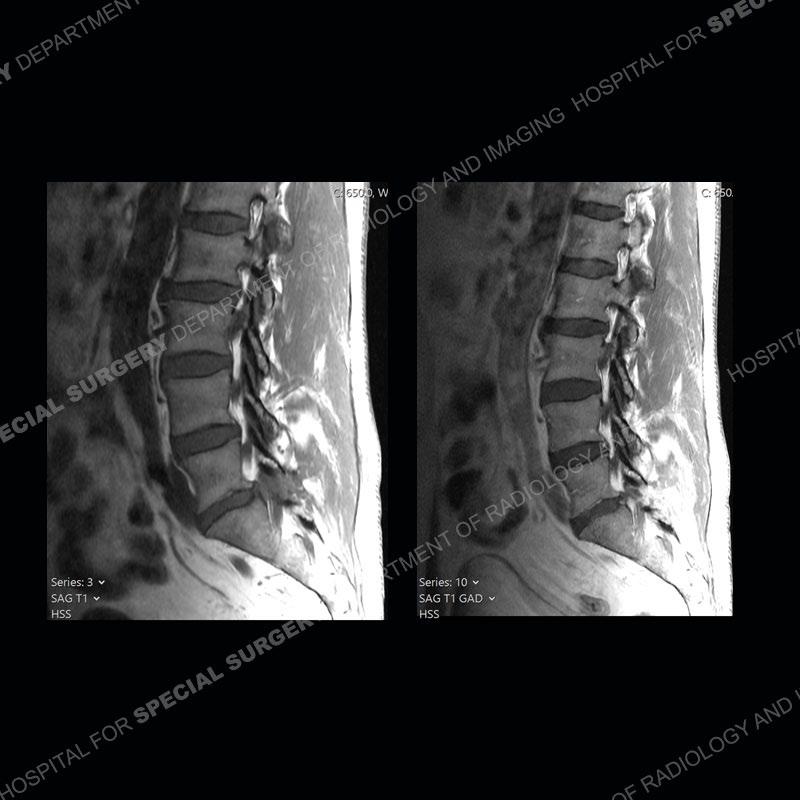

Post operative changes are seen on the left side at L5-S1 where there is near complete removal of the left sided L5 lamina, partial resection of the left L5-S1 facet joint, and resection of the left sided ligamentum flavum. In the anterolateral epidural space about the subarticular recess is a mass that demonstrates similar T1 and T2 signal characteristics to the adjacent degenerated disc. There is enhancement about the periphery of the mass, but the majority of this somewhat geographic or polyploid mass demonstrates no enhancement. The mass exerts prominent mass effect on the left S1 axillary sleeve/proximal nerve root. The left S1 nerve root shows enlargement and increased enhancement as compared to the contralateral right side.

Not as much of a diagnostic dilemma as some other cases but more so just a very nice example of what can be a difficult assessment at times. The evaluation of granulation tissue/scar/epidural fibrosis vs. disc herniation particularly in the earlier post operative period can be very difficult. Clues that can assist in identifying a disc herniation are a more geographic or polypoid nature to the mass, signal characteristics similar to the adjacent degenerated disc, mass effect upon the thecal sac/adjacent neural structures, and a typical enhancement pattern. As the disc material is avascular, as long as imaging is performed in a relatively rapid fashion after contrast administration (within 20-30 minutes), the granulation tissue around the disc will enhance but the disc material itself will not. If there is a marked delay between contrast administration and imaging, there may be diffusion of contrast into the disc making the assessment very difficult. The marked utility of contrast to help delineate disc vs. scar has led to our institution employing contrast fairly uniformly within the first two years following surgery.

The scar tissue in the setting of prior disc removal will be present in the anterior and anteriorlateral aspect of the epidural space. The signal characteristics can be somewhat variable from slightly more T2 hyperintense earlier on to T2 hypointense as the scar matures. However, the signal does not tend to follow the adjacent degenerated disc. The scar can produce mass effect, but it does not have to do so. In addition, at times the scar may be associated with a retraction of the adjacent thecal sac. Given the vascular nature of the scar there is typically somewhat avid, uniform enhancement which occurs fairly rapidly after contrast administration and begins to diminish within 20 minutes or so. Trying to discern the difference between scar and disc is of paramount importance given the rather poor outcomes associated with resection of scar as compared to disc material.